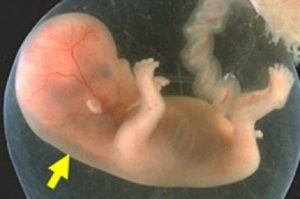

SIÊU ÂM ĐỘ MỜ DA GÁY: CÁC MẸ BẦU NÊN BIẾT CHO MỘT THAI KỲ MẠNH KHOẺ

Hiểu Về Siêu Âm Độ Mờ Da Gáy: Kiến Thức Quan Trọng Cho Thai Kỳ [...]